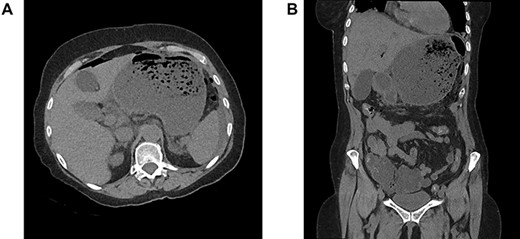

A 64-year-old woman was admitted in emergency for severe abdominal superior pain, nausea, dysphagia and fever. She explained having undergone a Nissen fundoplication 2 weeks earlier at another hospital, complicated a few days later by persistent dysphagia leading to redo-laparoscopy. Past medical history included hypertension, chronic obstructive pulmonary disease, hypothyroidism and appendectomy. On physical examination, she was septic (38.2°C, 110/70 mmHg, 110 bpm) with diffuse abdominal guarding. The blood test revealed a high grade of inflammation (C-reactive protein 17.35 mg/dL, white blood count 20.9 1000/mm3, lactic acid 3.2 mmol/L). The computed tomography scanner showed signs of perforation with hugely dilated stomach (Fig. 1A and B). Laparoscopic exploration attested to a generalized purulent peritonitis. Surprisingly, we found also a gastric greater curvature plication leading to a pyloric obstruction (Fig. 2A and B). Dismantling the Nissen wrap and the gastric plication allowed to find the gastric perforation on the top of the wrap (Fig. 3A and B). Simple closure of the perforation and large peritoneal lavage were performed. Postoperative recovery was marked by a left subphrenic abscess resolved under antibiotherapy. The patient was discharged on postoperative day (POD) 22.